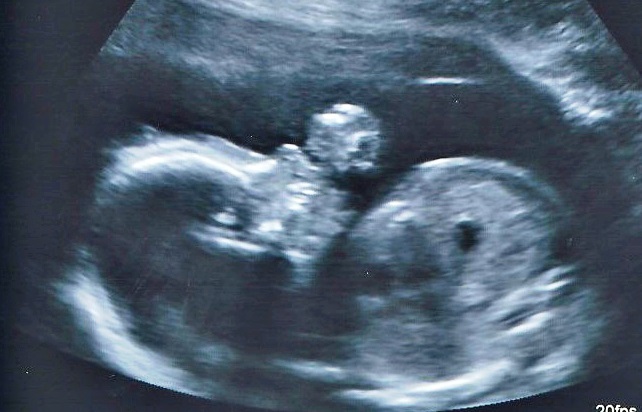

20 WKS

Attachment 23345

Attachment 23347